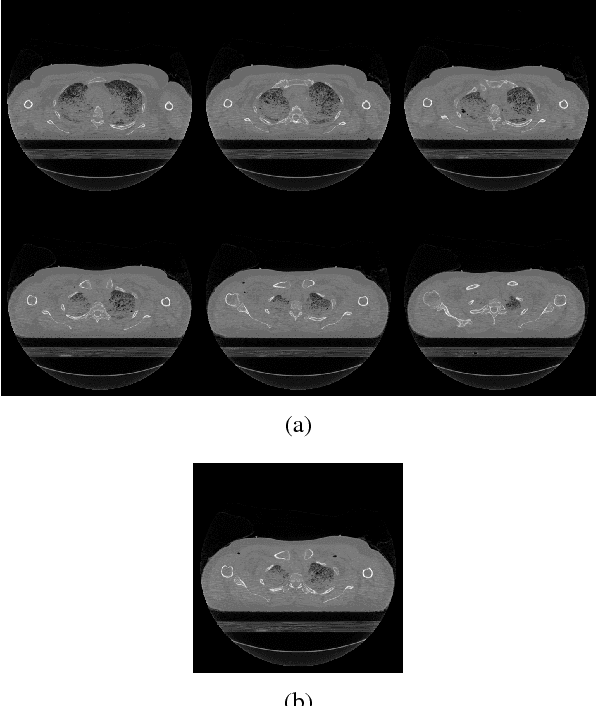

Abstract:Recent research in tomographic reconstruction is motivated by the need to efficiently recover detailed anatomy from limited measurements. One of the ways to compensate for the increasingly sparse sets of measurements is to exploit the information from templates, i.e., prior data available in the form of already reconstructed, structurally similar images. Towards this, previous work has exploited using a set of global and patch based dictionary priors. In this paper, we propose a global prior to improve both the speed and quality of tomographic reconstruction within a Compressive Sensing framework. We choose a set of potential representative 2D images referred to as templates, to build an eigenspace; this is subsequently used to guide the iterative reconstruction of a similar slice from sparse acquisition data. Our experiments across a diverse range of datasets show that reconstruction using an appropriate global prior, apart from being faster, gives a much lower reconstruction error when compared to the state of the art.